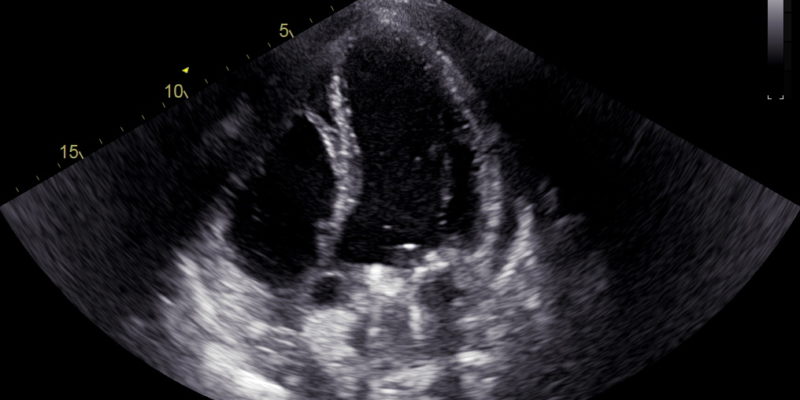

Porast broja oboljelih, novosti u slikovnim metodama i pristupima u liječenju te važnost uloge “Heart Team”-a predstavljaju temelj postojanja Radne skupine za bolesti srčanih zalistaka Hrvatskog kardiološkog društva.

Naša uloga je približiti izazove liječenja bolesnika s bolestima srčanih zalistaka s ciljem poboljšanja pravovremenog otkrivanja i učinkovitijeg liječenja.